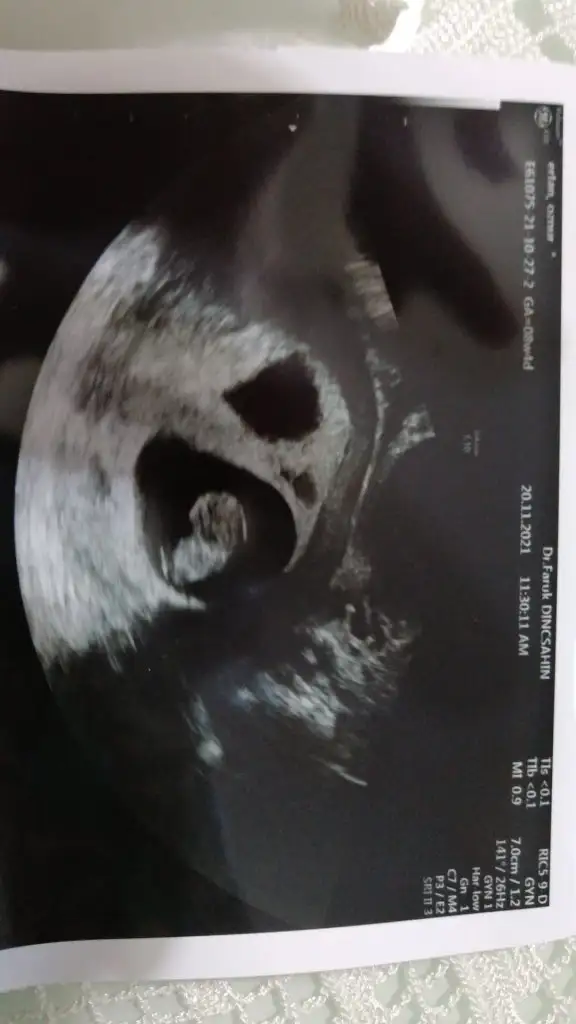

Gözünüz aydın inşallah sağlıkla kucağınıza nasip almayı da nasip etsin AllahMerhabalar kızlar.. Bugün kontrolüm vardı.. Öyle heyecanlı gittim ki anlatamam. Ve 2 bebeğimi de sağ salim gördüm maşallahları vardı. İnanamadım dondum kaldım. Bildiğiniz kafaları falan oluşmuş tu. Renkli görüntüde verdi doktorum. Orada da belli. Sizlerde paylaşmak istedim. 9.haftaya girdim artık. Hiç bir ilacımı kesmedi aynen devam dedi. 2 hafta sonra tekrar kontrole gideceğiz. İkizlerim benimle çok şükür sımsıkı tutunmuşlar bana.

Valla anlamadım ki ultrason görüntüsünün yanında öyle rakamlardan birşey anlamadık. birde renkli ultrason verdi. orada biri 4.0 diğeri 4.3 yazıyordu bizde bu herhalde dedik. görüntülerini de ekliyorum. renklileri ekleyemedim.Gerçekten inanılmaz bir şey canım.

CRL’de mi 4,3 cm yazıyor canım?

Benim 10+3 olmasına rağmen 3,12cm.

Bi yanlışlık olmalı.

Belki kese boyu falandır, olabilir mi?

Yok canım, ölçüm yapmamış burada.Valla anlamadım ki ultrason görüntüsünün yanında öyle rakamlardan birşey anlamadık. birde renkli ultrason verdi. orada biri 4.0 diğeri 4.3 yazıyordu bizde bu herhalde dedik. görüntülerini de ekliyorum. renklileri ekleyemedim.

Ay yok yok canım buldum şimdi ölçmüş yaa bir sürü ultrason görüntüsü verdi doktor 2 sinde de ölçmüş. Biri 1. 84 diğeri 1.85 miş crl öyle yazıyor. Baş ile popo ölçümü yapılmış.Gerçekten inanılmaz bir şey canım.